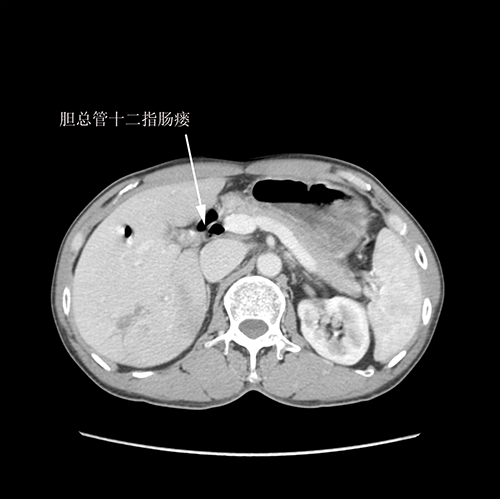

右肝内胆管结石、 胆管十二指肠瘘--S67肝切除、胆肠吻合、十二指肠瘘修补